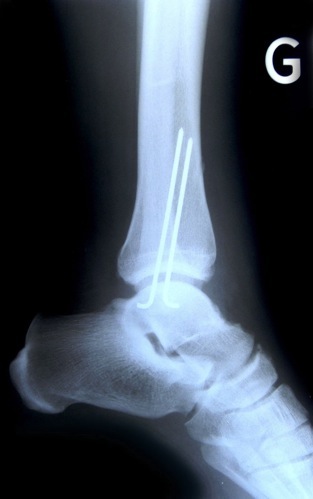

Analyse de radiographies

Analyse différentes radiographies. Essaye de reconnaître:

les différentes parties représentées: os, articulations,...

les malformations, les déplacements, les fractures.

l’âge des sujets: zones de croissances.